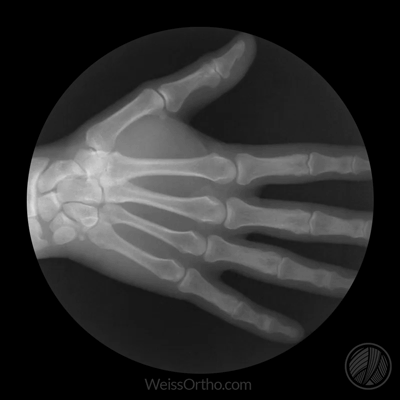

Met X-rays of Röntgenstralen kunnen we in ons lichaam kijken, maar we kennen het meestal gewoon als een foto: een stilstaand beeld van botten of gewrichten. Door fluoroscopie kunnen echter ook bewegende beelden gemaakt worden.

Ontwerper en fotograaf Cameron Drake ging aan de slag met beelden van het orthopedisch instituut van Dr. Noah Weiss in de V.S. (Weis Orthopaedics). Op zijn blog legt Drake uit hoe hij de beelden die Dr. Weiss gemaakt heeft van zijn patiënten omgezet heeft in deze gifs.

Zou ook heel interessant zijn om zo’n reeks te zien van gewrichten die aangetast zijn door Spondylitis Ankylosans (ziekte van Bechterew).